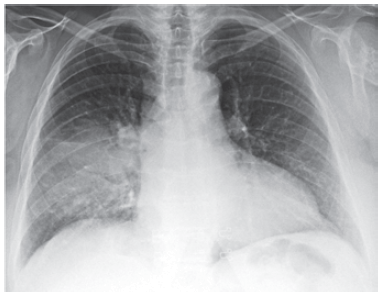

Mulher de 42 anos, sem comorbidades, apresenta quadro de 3 dias de anorexia, prostração, febre e tosse. Não há espirros, rinorreia ou disfonia. Ela nega tabagismo, etilismo e uso de drogas. Exame físico: temperatura: 38,5 ºC; frequência respiratória: 18 ipm; pressão arterial: 120 x 80; frequência cardíaca: 95 bpm; oximetria de pulso com saturação de 97%; ausculta pulmonar com crepitações em metade de hemitórax direito. Teste rápido de COVID e influenza são negativos. A radiografia de tórax realizada é mostrada a seguir.

Com os dados descritos, é correto afirmar: